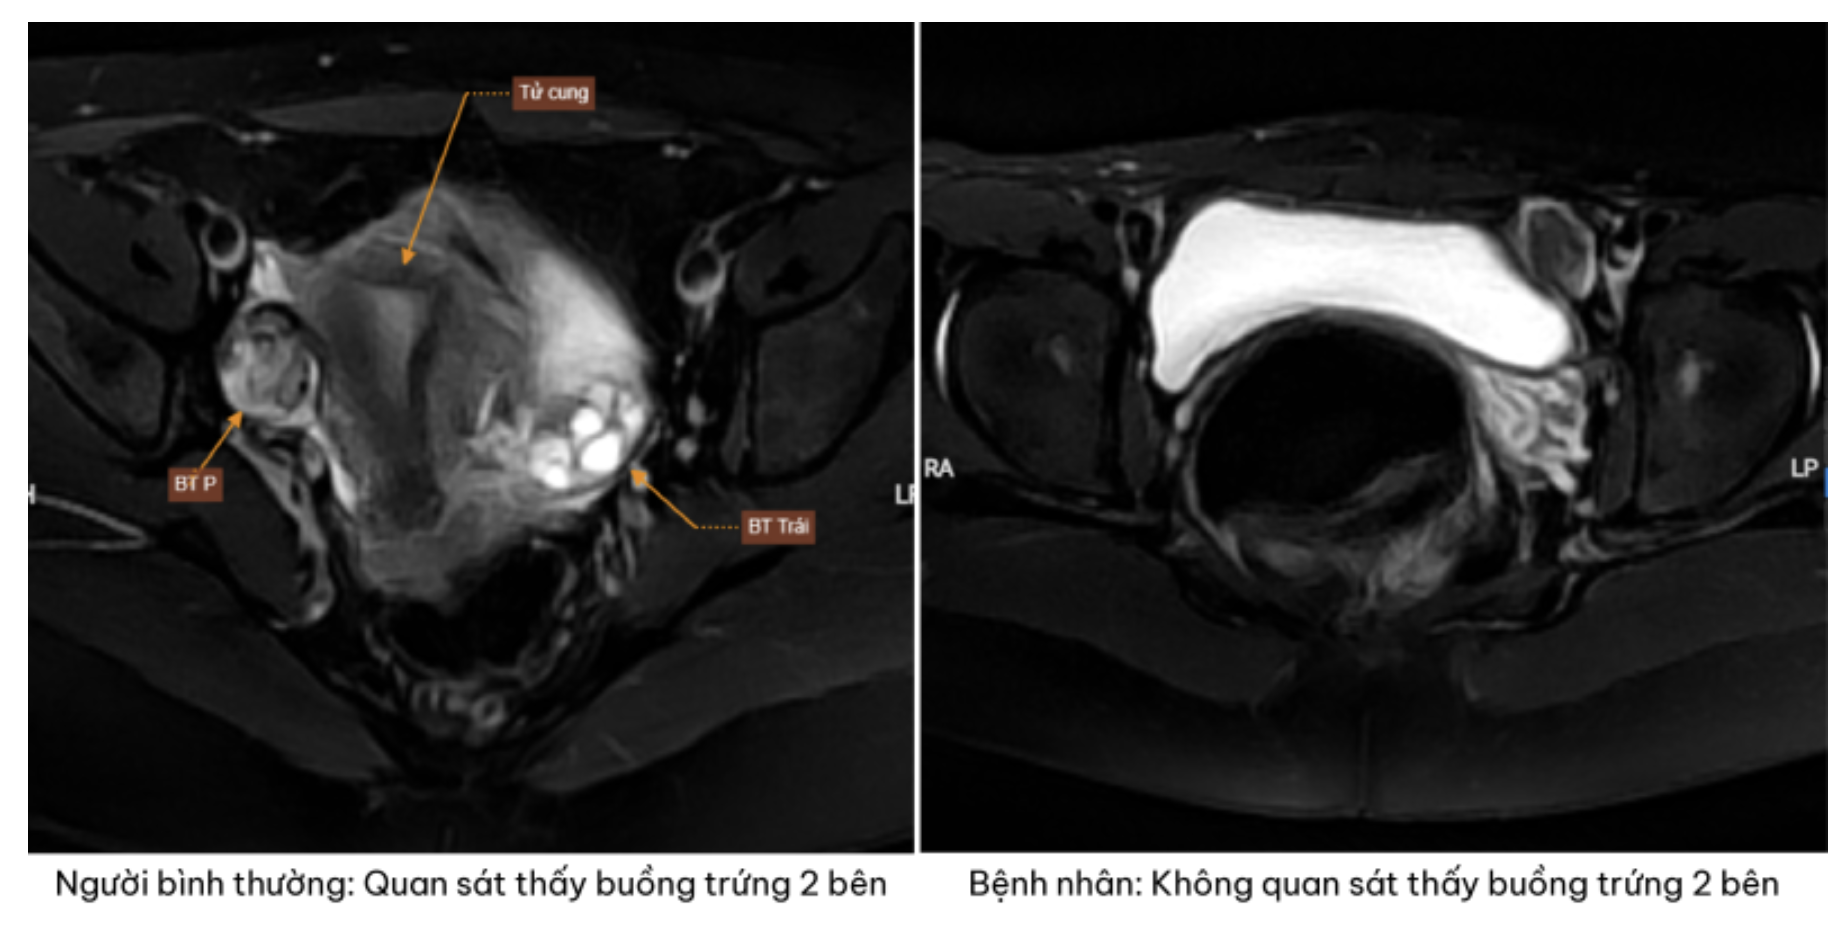

Trên hình ảnh chụp cộng hưởng từ phát hiện bệnh nhân không có tử cung và buồng trứng hai bên - Ảnh: BVCC

Kết quả siêu âm và chụp cộng hưởng từ cho thấy một thực tế khiến cả gia đình bàng hoàng không phát hiện hình ảnh tử cung và buồng trứng ở cả hai bên.